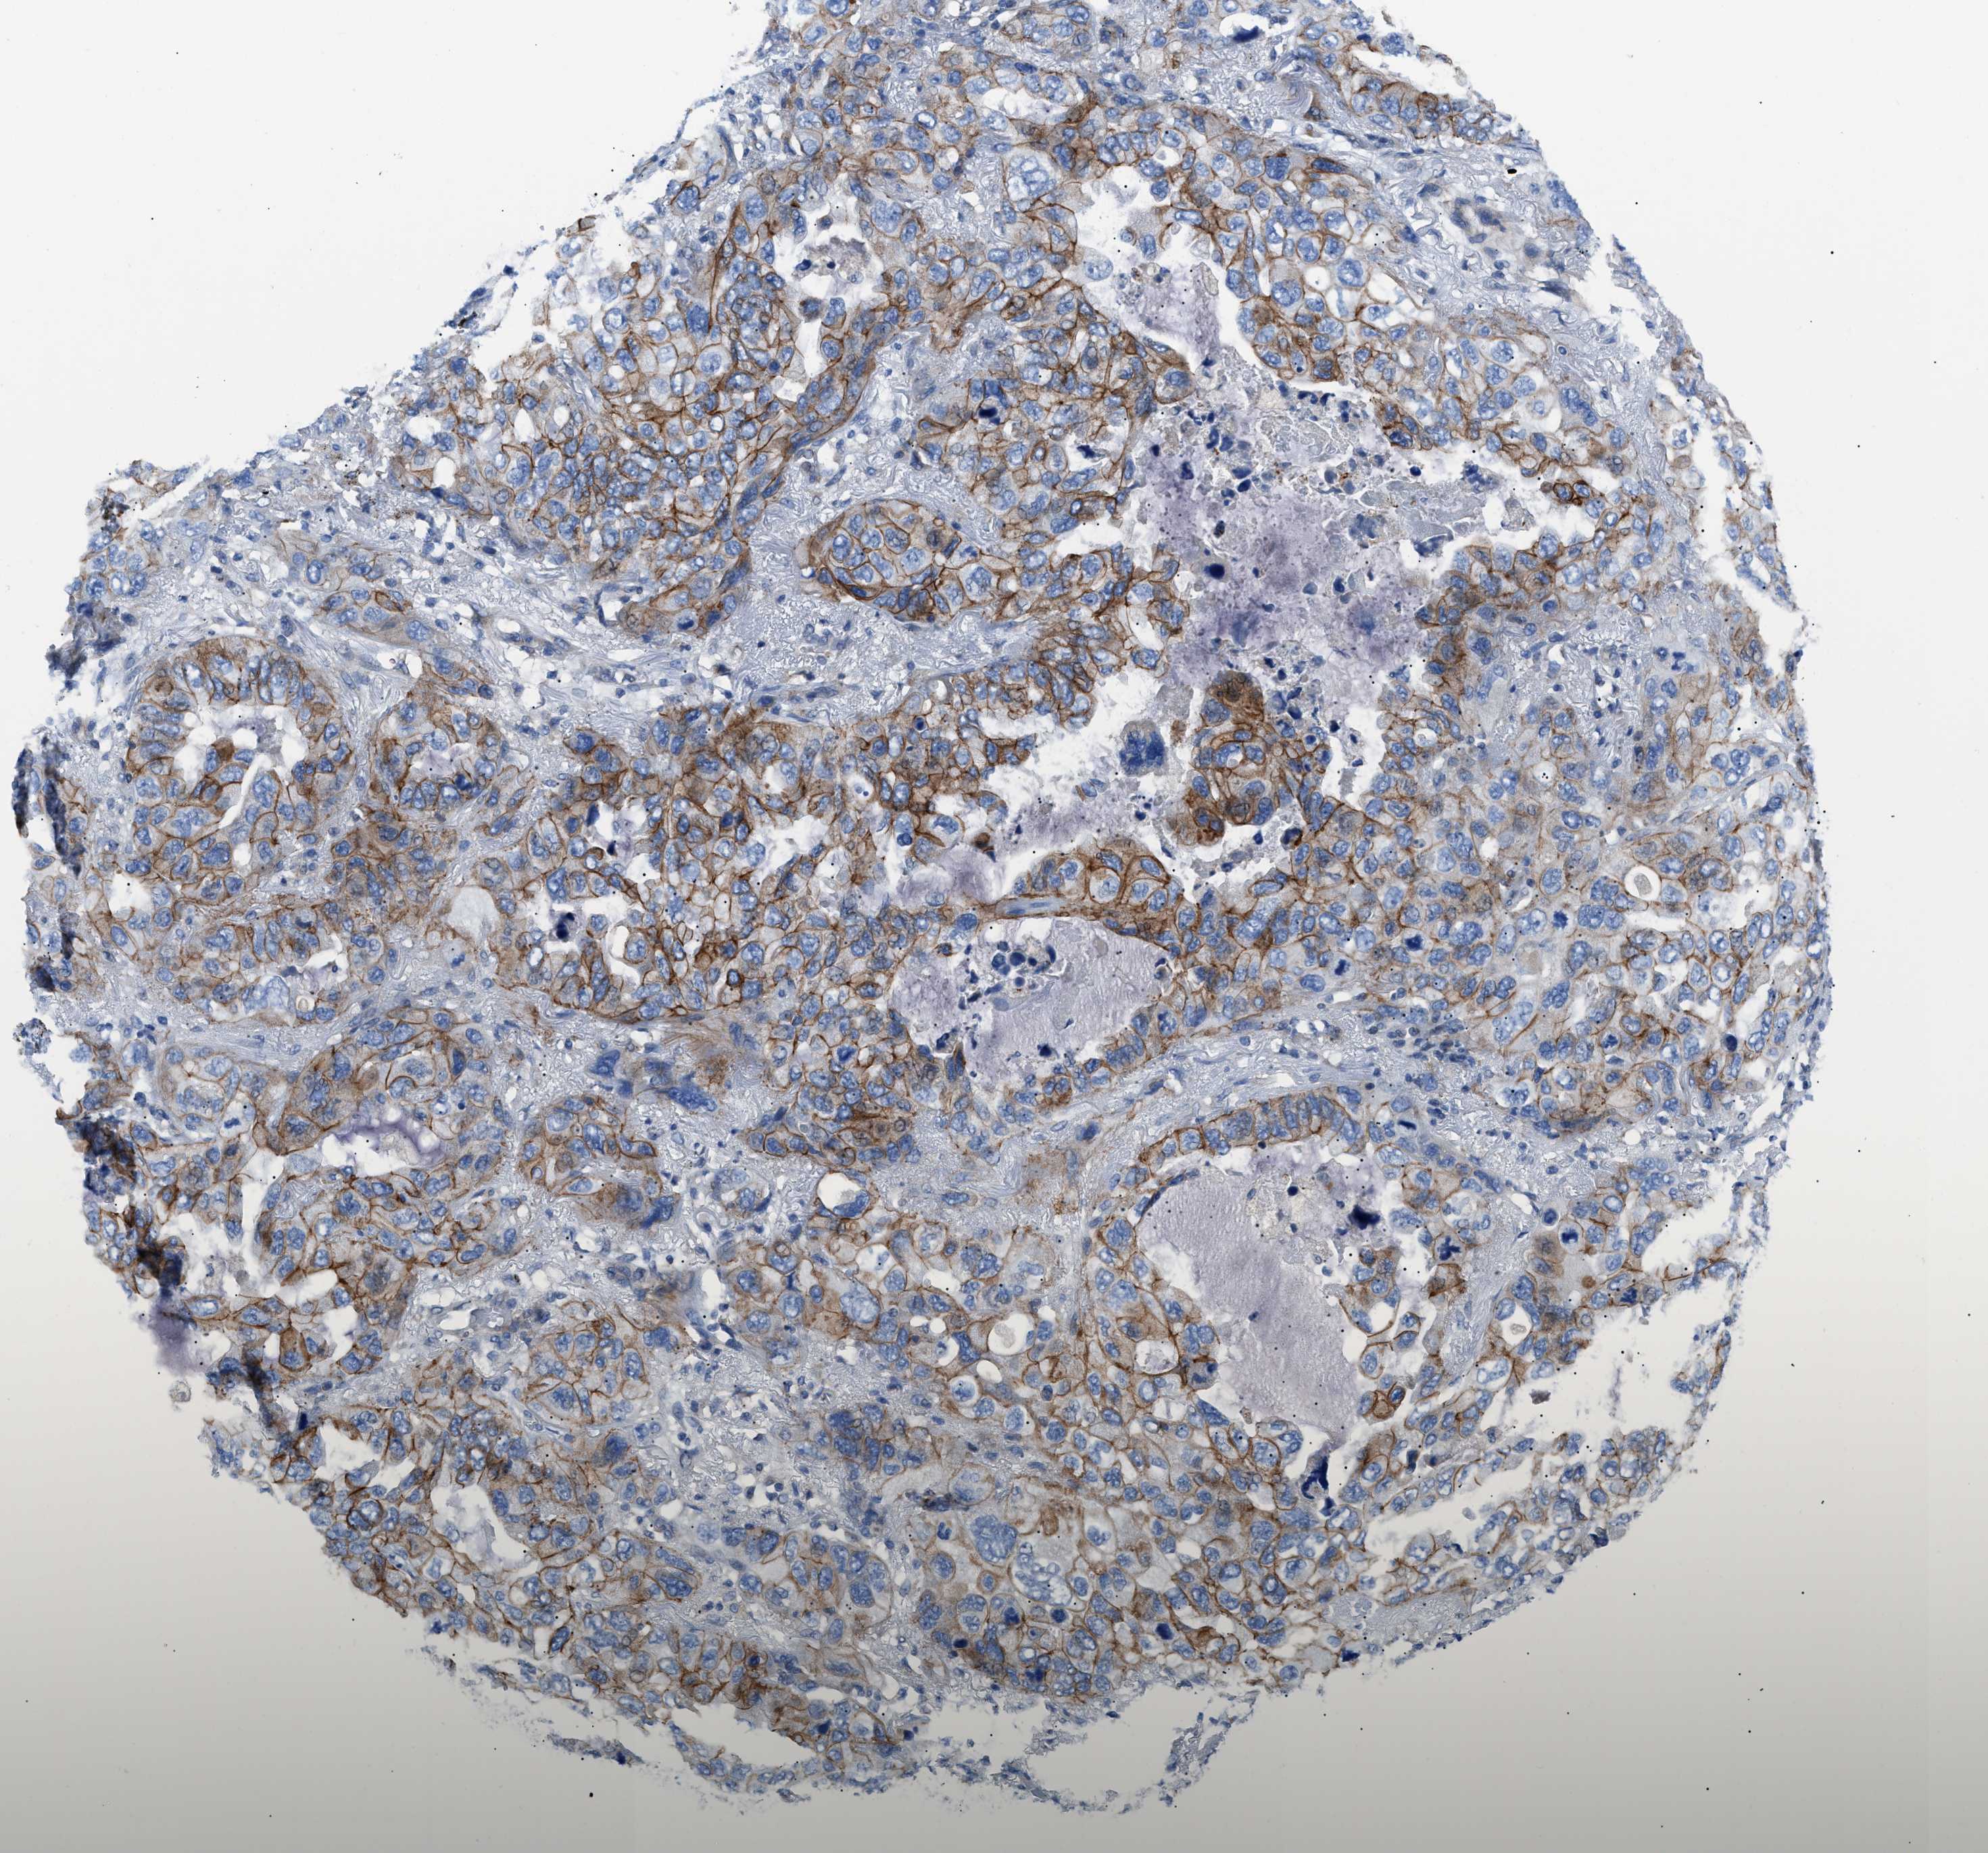

CANCER LUNG CANCER Show tissue menu

Lung cancer

Human cancer

Lung adenocarcinoma

Lung squamous cell carcinoma